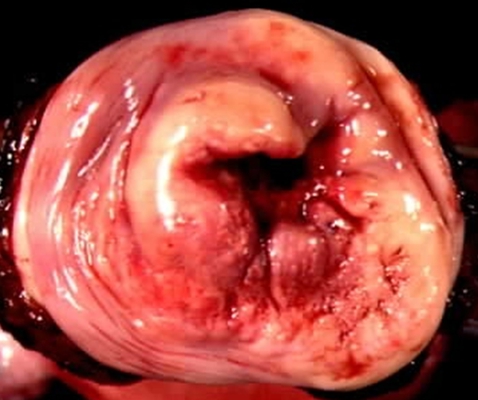

子宮頸癌圖片

宮頸癌

宮頸癌

宮頸癌

宮頸癌

宮頸癌

宮頸癌

宮頸癌

宮頸癌

宮頸癌

宮頸癌

宮頸癌

宮頸癌

宮頸癌

宮頸癌

宮頸癌

宮頸癌

宮頸癌

宮頸癌

宮頸癌

宮頸癌